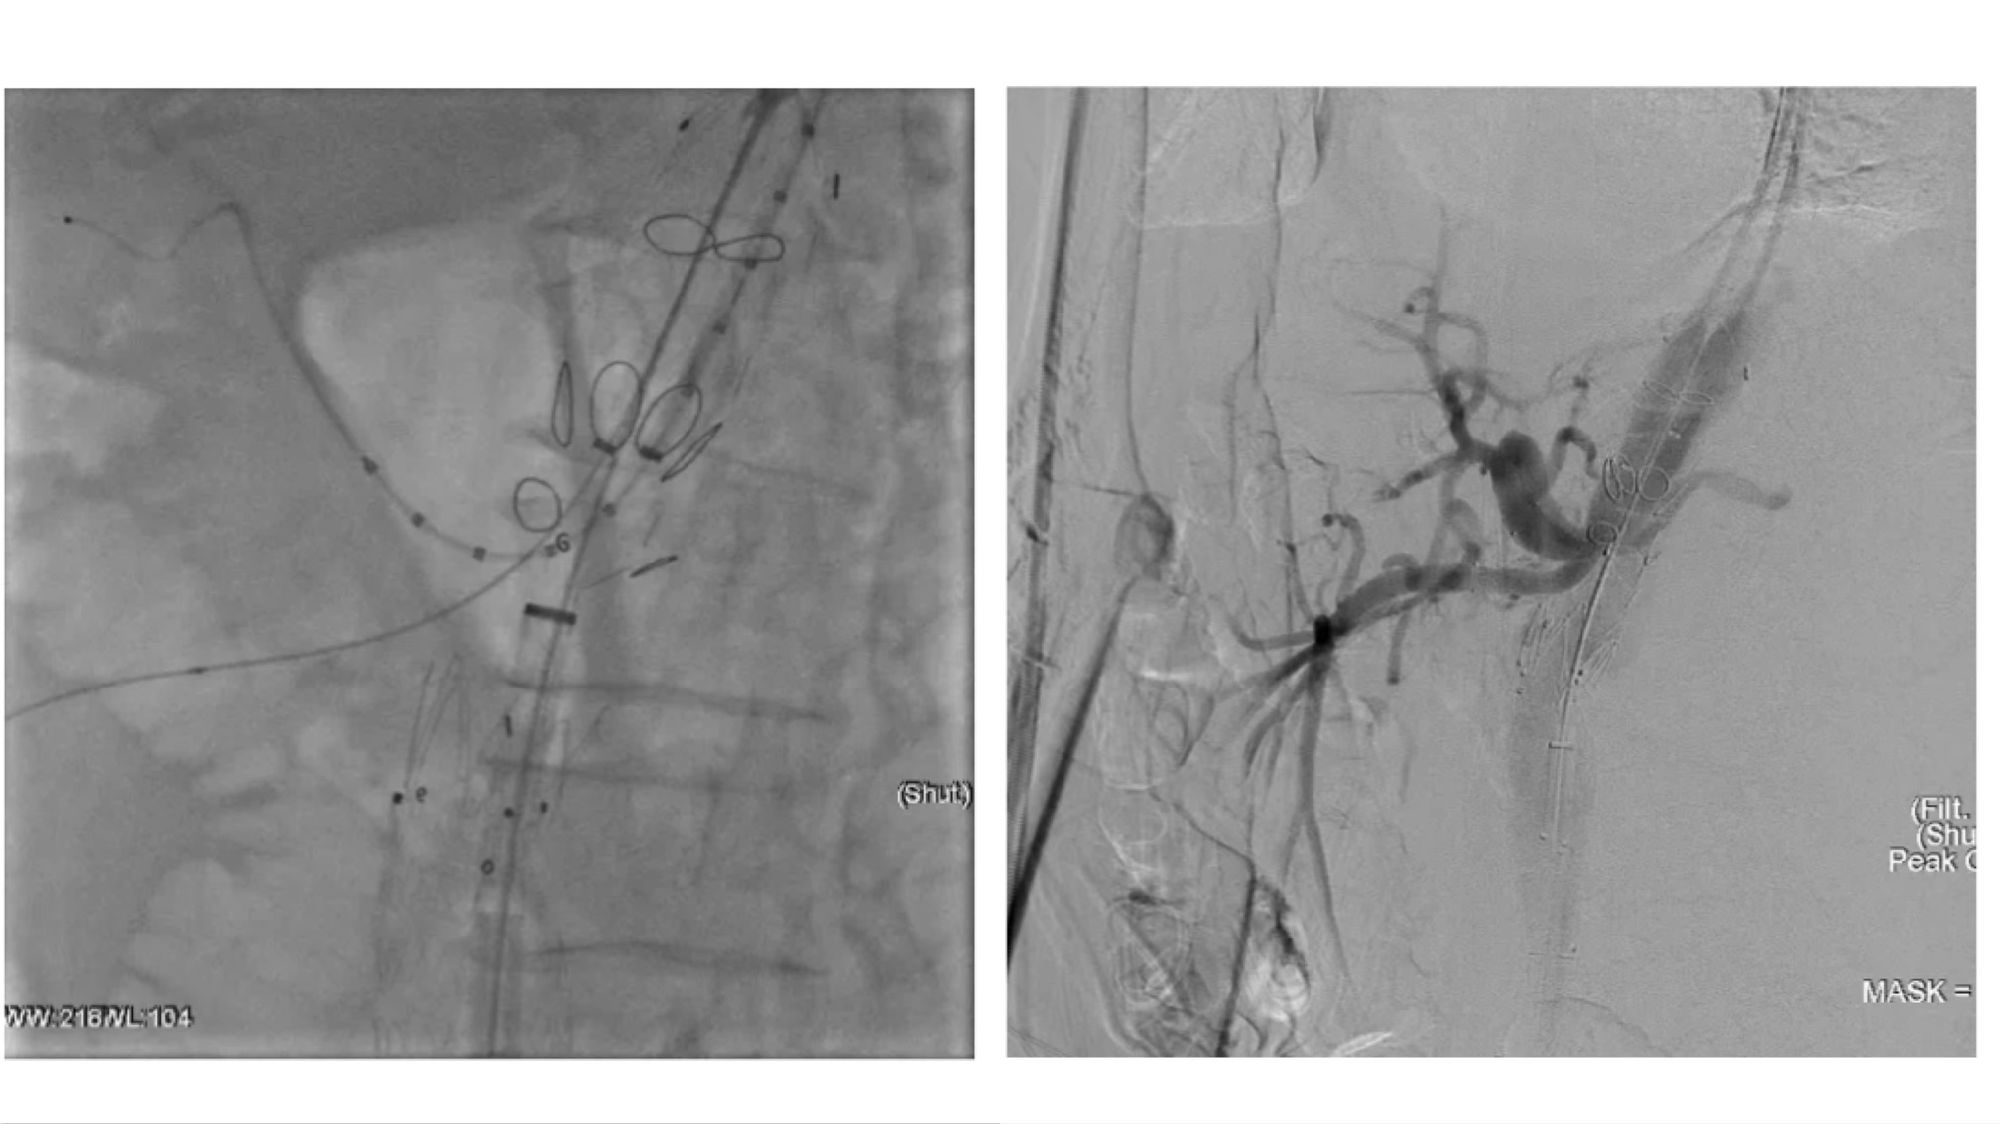

腔内重建腹腔干和肠系膜上动脉

腔内重建右肾和左肾动脉

(右肾开口处重度狭窄,左肾烟囱支架术后增加了手术难度)

术后造影及出院前随访:

患者胸腹主动脉瘤隔绝完全,支架位置及形态良好,各分支动脉重建后血流通畅,无内漏发生。